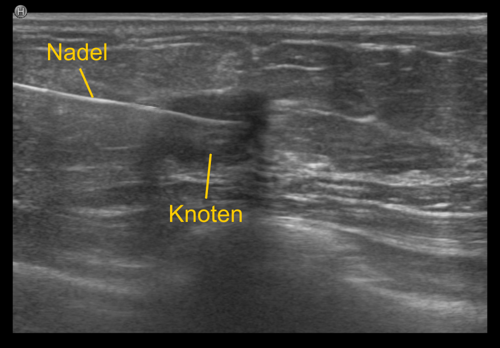

Bei der Gewebeprobeentnahme, der sogenannten 'Biopsie', wird eine dünne Nadel in den verdächtigen Bezirk eingebracht, und eine oder mehrere Gewebeproben entnommen. Diese Proben werden anschließend vom Pathologen aufbereitet und unter dem Mikroskop genau analysiert. Die Entnahmeregion wird üblicherweise mit einem kleinen Markierungsklipp gekennzeichnet, damit die Stelle bei Bedarf jederzeit wieder auffindbar ist.

Die unterschiedlichen Methoden richten sich nach der Bildgebung. Ist die verdächtige Region im Ultraschall sichtbar, wird die ultraschallgezielte Gewebeprobeentnahme bevorzugt, da sie relativ einfach und rasch (üblicherweise zwischen 15 bis 20 Minuten) durchführbar ist.